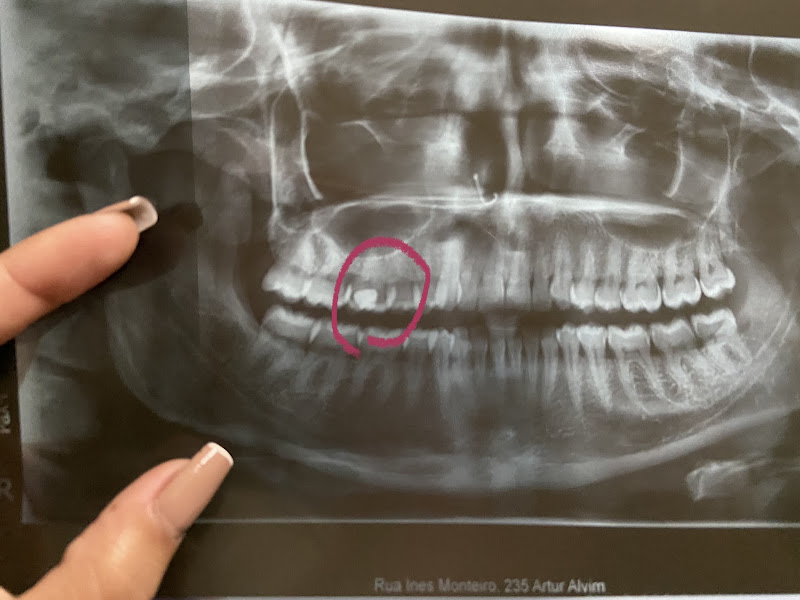

Puro descaso, dentista bateu tanto no meu dente que que estava quebrado que poderia ter quebrado mais ainda, enfim depois de passar no máximo 2 minutos na avaliação, ele disse que teria que fazer canal, fui em outro fazer avaliação pra ter certeza, e para minha surpresa disseram que apenas seria necessário uma a restauração, e foi bem rápido e prático, era apenas um pedaço bem pequeno que quebrou, minúsculo não necessitava de canal, disseram que meus dentes são ótimos! Bem melhor que o Dodoclin! Ou seja só quer ganhar dinheiro, bem provável que o canal deve ser feito igual o atendimento, péssimo! Passo bem longe dai

Atendimento na recepção bom porém dentista de péssima qualidade , passei com a Janaína meu dente só precisava de uma restauração , fiquei dias com dor ,fiz outro rx, e estou com uma lesão no dente ! Eu não precisava de quase nada e eles acabaram com meu dente ! Vou atrás dos meus direitos pq profissionais assim nem precisava se formar .